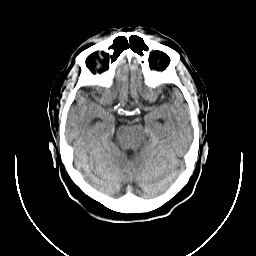

CT Study #1 -- Slice #9

[Home][Help][Clinical][Tour 1] Slice 9